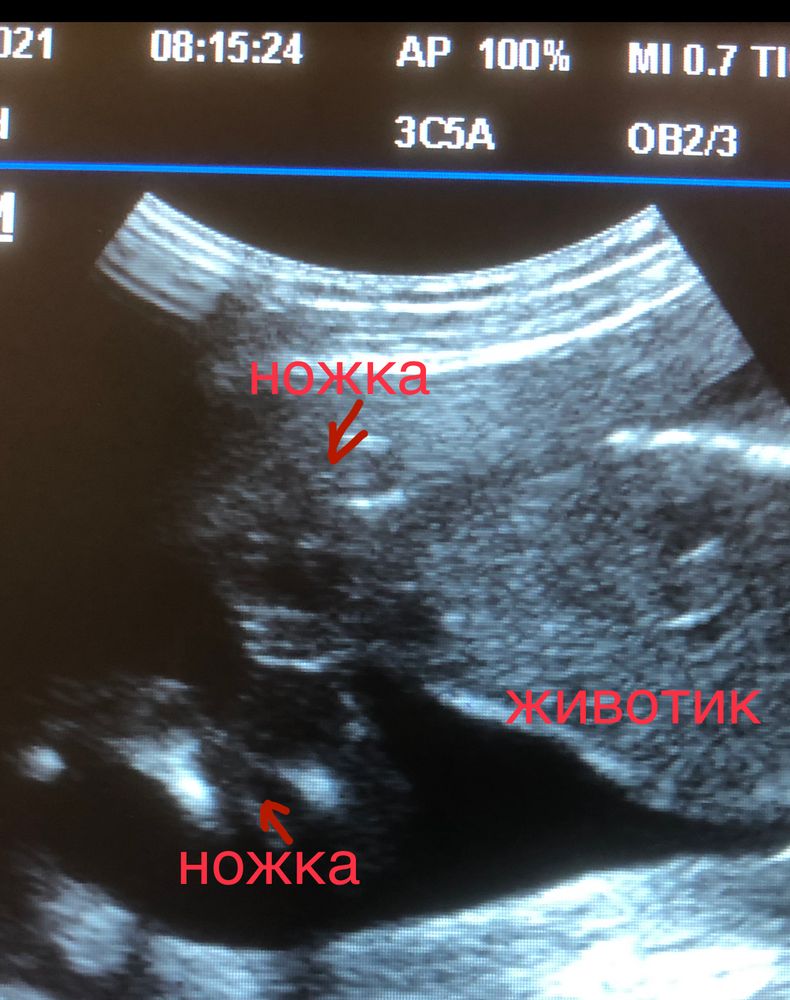

Привет, девочки! УЗИ в 20 недель и 3 дня, подтвердили девочку))) Готовлю всей семье сюрприз-вечеринку, где муж лопнет шарик с конфети, поэтому пока держу всё в секрете. Ну и конечно, все высказывают свои предположения по поводу пола, так вот абсолютно ВСЕ в семье уверенны, что будет мальчик!!! Естественно я начала сомневаться 🙈🙈🙈 Кого видите вы????